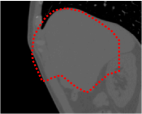

An example of CT/CBCT and MR/CBCT registration results are shown in figures 3 and 4, respectively. For both cases, the CBCT image (first column) was acquired intra-operatively after needle insertions and was employed as a reference for image registration. The pre-operative image is displayed before registration (second column), after PM-EA (third column) and after PM-EA+Evo (fourth column). The occurrence of patch shifts is reported for each spatial direction in panels (m–o): for each histogram, the shift with maximal occurrence is shown by the red dashed line. For panels (a–l), a ROI — manually defined on the CBCT image/encompassing the liver — is shown using red dash lines. Our visualization shows an improved correspondence of the contour of the liver with the manually defined liver boundary when the PM-EA solution is employed (see 3(c,g,k) and 4(c,g,k)). Moreover, an even better correspondence of the contour is observable using the PM-EA+Evo solution (see 3(d,h,l) and 4(d,h,l)).

Trans.

[X-Y]

CBCT

(a)

CT / No registration

(b)

CT / PM-EA

(c)

CT / PM-EA+Evo

(d)

Sag.

[X-Z]

(e)

(f)

(g)

(h)

Cor.

[Y-Z]

(i)

(j)

(k)

(l)

(m)

(n)

(o)